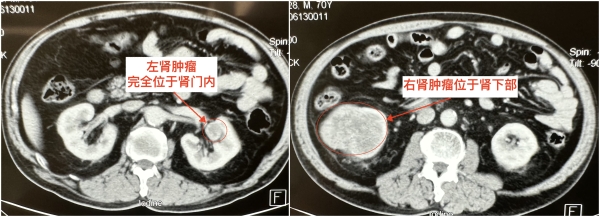

2023年6月15日,患者任某检查发现两侧肾脏均有不明肿块,右侧肿块位于肾下级,大小8cm×7cm×5cm,左侧肿块位于肾门内,大小2.5cm×2cm×2cm,并被肾实质完全覆盖。这对于一位70岁的老人来说犹如晴天霹雳,家里人也十分着急,辗转多家医院均被告知保留肾脏手术难度大,术后可能需要依靠透析生存。后患者经多方打听,了解到西安交大二附院泌尿外科治疗肾癌临床经验丰富,遂经种铁主任门诊收住入院。

患者入院后由肾肿瘤专业组付德来副主任医师、唐骁爽主治医师具体负责,经完善相关检查,科室术前讨论一致认为患者双侧肾癌诊断明确,有手术适应征,无手术禁忌征,建议积极手术治疗,手术方式首选保留肾功能的肾部分切除术。种铁教授为患者仔细分析病情,患者右侧肾癌占据右肾整个下半部,需行半肾切除,术中需严格执行无瘤原则,完整切除肿瘤,并严密缝合止血。左侧肾癌完全位于肾窦内,位置刁钻,与肾动静脉、肾盂肾盏关系密切,术中需轻柔操作,在切除肿瘤的同时避免副损伤。我院引进的最新一代达芬奇手术机器人在血管解剖、肿瘤切除及组织重建方面具有明显优势,可尽可能缩短肾脏缺血时间,最大限度保护肾脏功能,建议行机器人辅助腹腔镜双侧肾部分切除术。